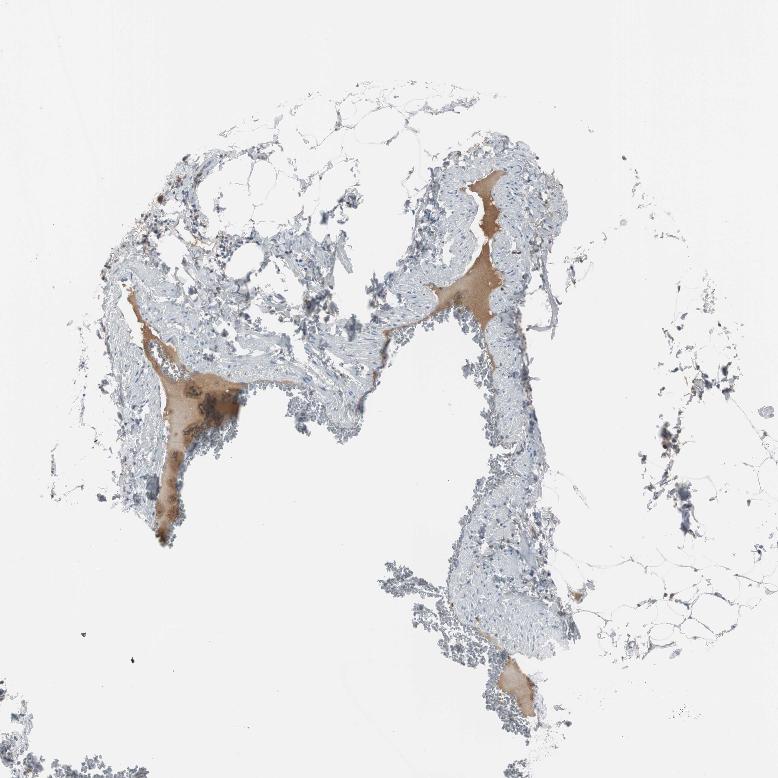

ADIPOSE TISSUE - Antibody stainingi

Antibody staining in the annotated cell types in the current human tissue is reported as not detected, low, medium, or high, based on conventional immunohistochemistry profiling in selected tissues. This score is based on the combination of the staining intensity and fraction of stained cells.

Each image is clickable and will lead to virtual microscopy that enables deeper exploration of all samples and also displays staining intensity scores, fraction scores and subcellular localization as well as patient and tissue information for each sample.

Antibody HPA005825

Adipocytes Not detected